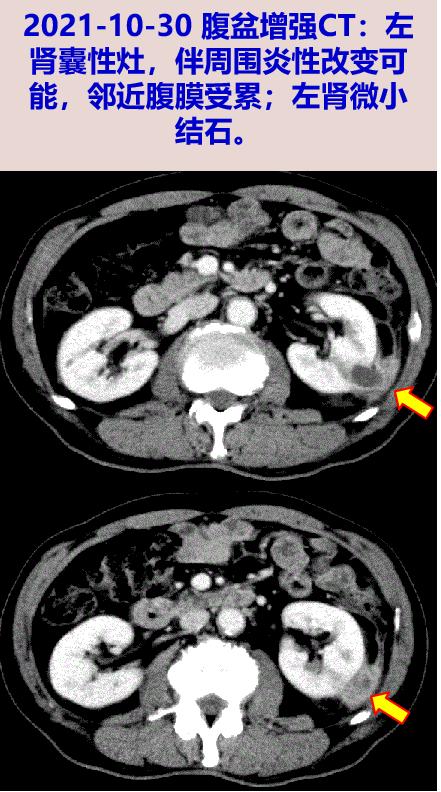

2021-10-30 随访腹盆增强CT:左肾囊性灶(较前缩小),伴周围炎性改变可能,邻近腹膜受累。